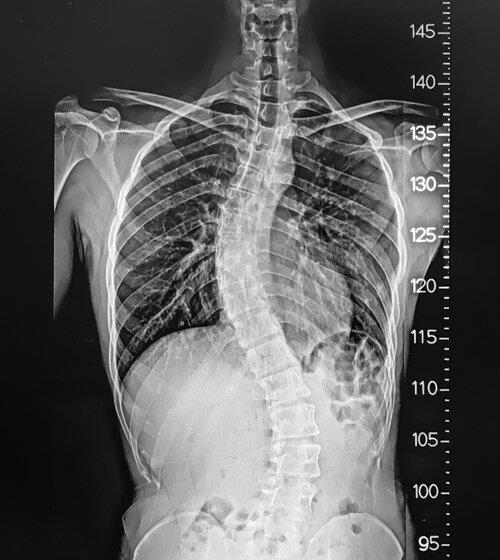

Disc Herniation Arizona/Disc Herniation Phoenix

To remove the damaged Disc Herniation in Arizona's healthcare center, Dr. Andrew Chung successfully performed the spine surgery using the latest micro-invasive techniques and surgical tools. He is an experienced surgeon-scientist who uses different techniques and treatments to reduce neck and back pain. At the Banner Health Clinic, he manages many patients with the help of staff, and after the surgery, his priority is to recover the patient's health condition. To know more, click on the website!

In Phoenix, Disc herniation treatment is available at the Banner Health Clinic. If you avoid a spine problem, it can be dangerous for your health. Through robotic surgery, Dr. Andrew Chung removed the damaged tissues by applying the latest science-based techniques to reduce pain. If you want a proper treatment for removing your spine injury, you can book your appointment at the healthcare center where surgeon scientists provide emergency treatments for the patients. For more details, click on the website!